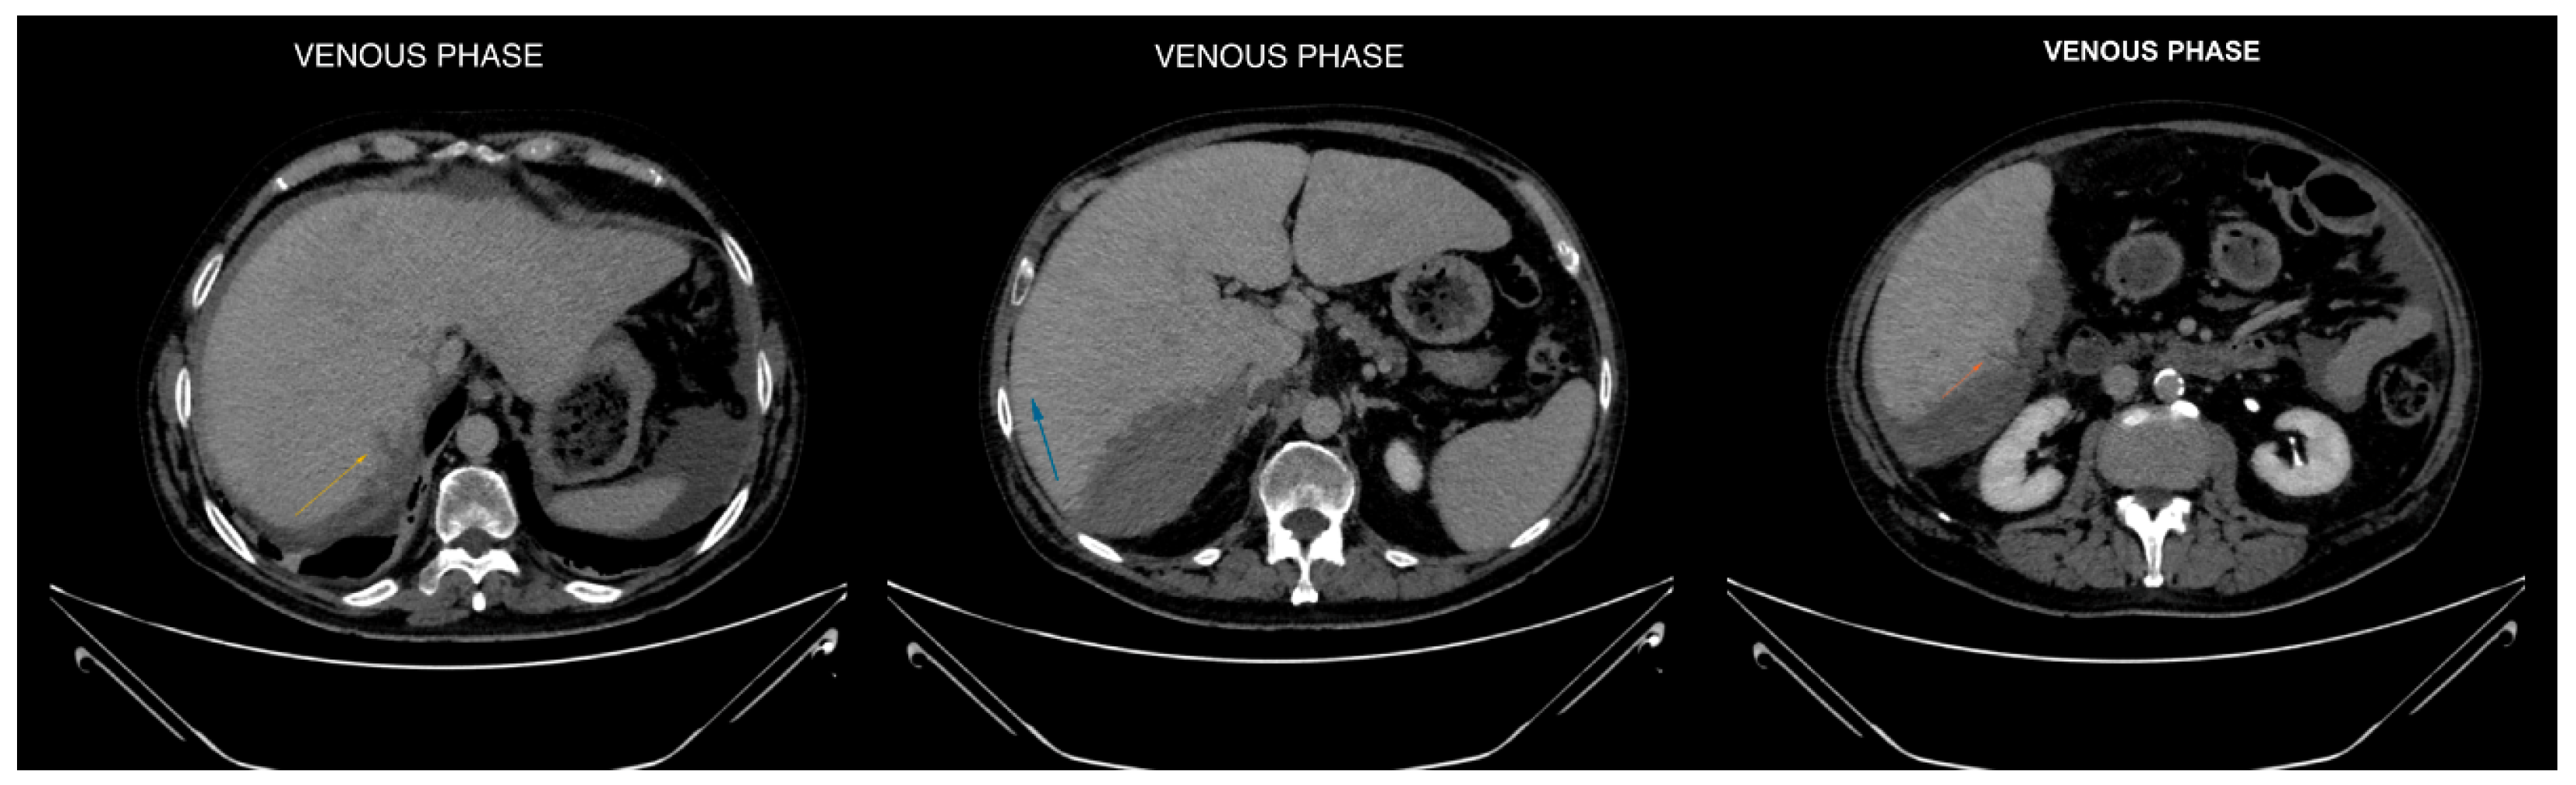

Figure 3. Axial CT images in venous phase focused on liver segments VI and VII, revealing hypodense subcapsular streaks (maximum extension of approximately 1.5 cm). These findings are consistent with hepatic lesions, likely indicative of a laceration [1,2].